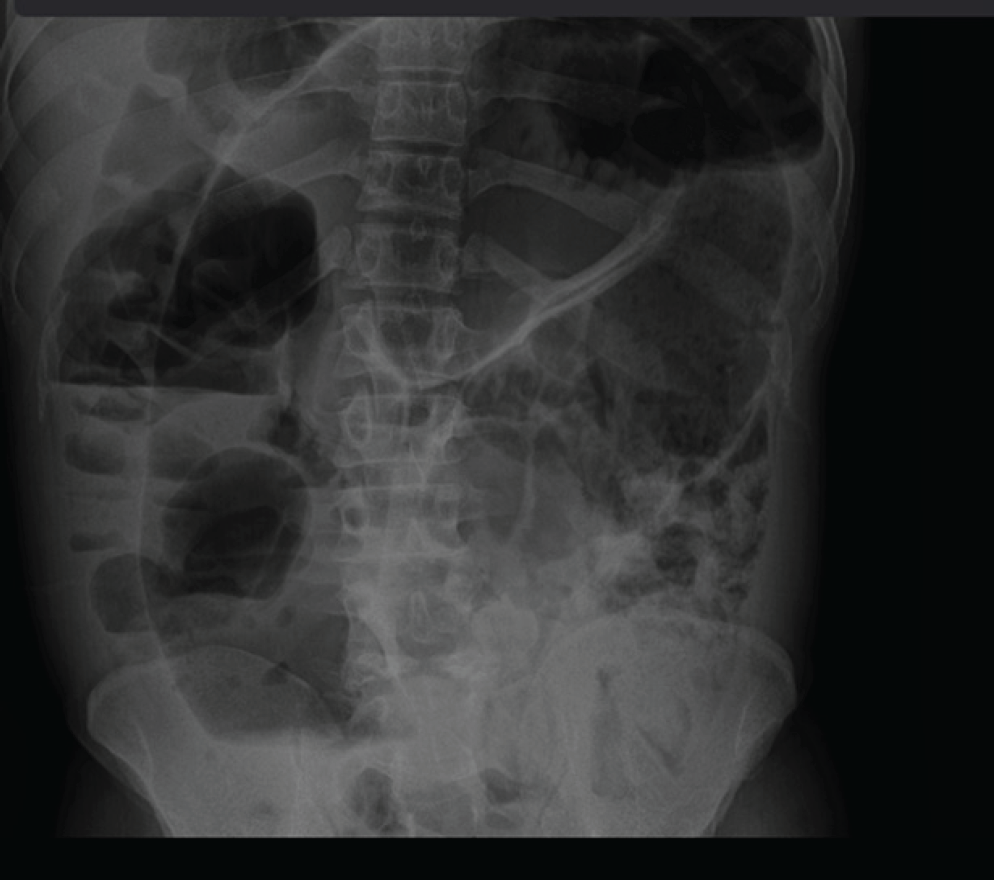

We present a case of a 33 year old, pregnant woman, Gravida 4, Para 3, at 32 weeks of gestation, who presented with abdominal pain, distension, and tenderness. A Plain abdominal X-ray showed a dilated loop of the sigmoid colon. This was her second admission with similar symptoms. Having previously diagnosed with sigmoid volvulus one month earlier, she was treated conservatively, recovered, and discharged. On this admission she was diagnosed with recurrent sigmoid volvulus, after stabilization she underwent laparotomy which revealed sigmoid colon volvulus at 180 degrees twist. A resection of redundant sigmoid was done, resulting in uneventful postoperative care, discharge, and follow-up.